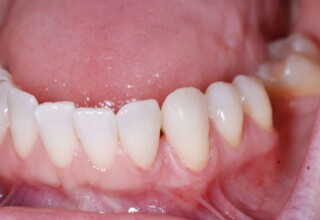

Αποκατάσταση Οπίσθιου Απονευρωμένου Δοντιού με Ανασύσταση Σύνθετης Ρητίνης

Η συνήθης αποκατάσταση ενός απονευρωμένου οπισθίου δοντιού είναι με μια στεφάνη. Ο κύριος λόγος είναι η προληπτική προστασία από κάταγμα και την επακόλουθη εξαγωγή. Σε πολύ συγκεκριμένες περιπτώσεις όπου εξειδικευμένα κριτήρια (κυρίως η ποσότητα της εναπομείνουσας οδοντικής ουσίας) ικανοποιούνται ή όταν η οικονομική δυνατότητα του ασθενή το επιβάλει, μια εκτεταμένη ανασύσταση συνθέτης ρητίνης μπορεί ν’αποκαταστήσει την αισθητική και λειτουργικότητα του δοντιού.